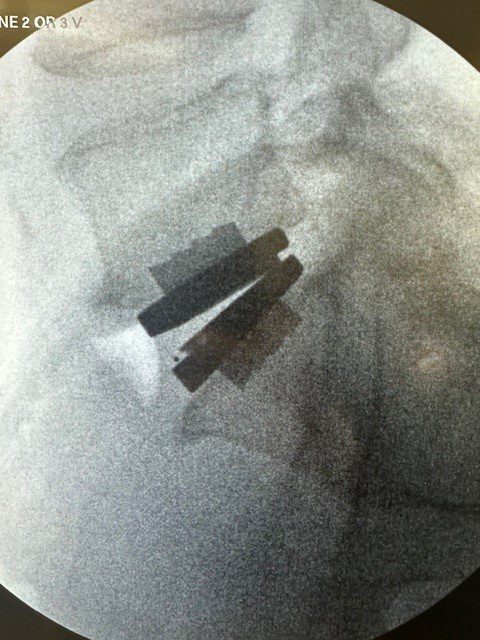

Mike Hewitt, a 55-year-old retired Air Force veteran, didn’t think he would ever again be able to enjoy running, golfing, or playing with his grandchildren. For over two decades, he lived with chronic back pain from a previous injury. Despite years of physical therapy and treatments, his pain persisted. Thanks to a recent prodisc L TDR surgery, he is regaining his quality of life.

“With the continual improvement in insurance coverage, more of my patients will be able to benefit from disc replacement technology... Using a minimally invasive anterior approach, my patients also benefit from a much faster recovery and return to active life, while decreasing the likelihood of adjacent level degeneration.”